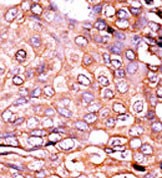

Product Image

- Formalin-fixed and paraffin-embedded human cancer tissue reacted with the primary antibody, which was peroxidase-conjugated to the secondary antibody, followed by AEC staining. This data demonstrates the use of this antibody for immunohistochemistry; clinical relevance has not been evaluated. BC = breast carcinoma; HC = hepatocarcinoma.